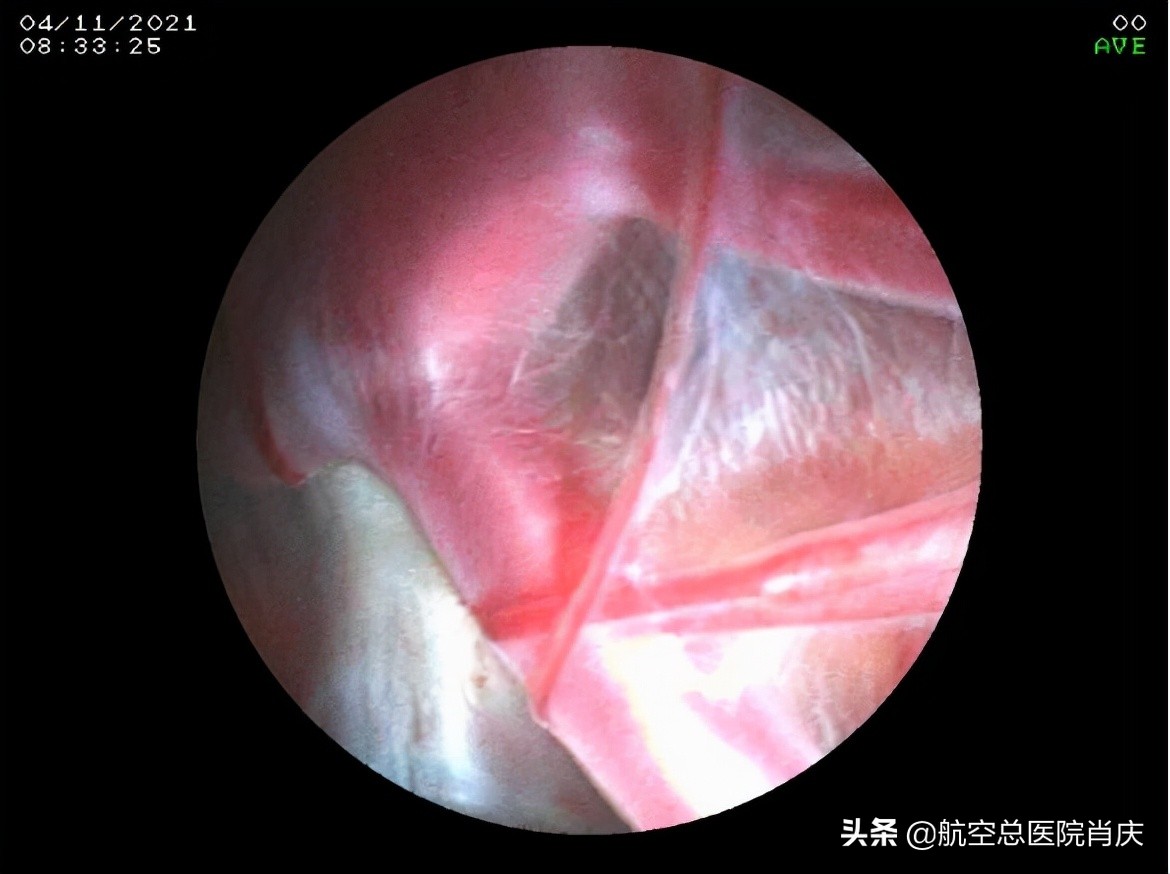

(自基底池所见左侧颞极囊肿壁)

(自基底池所见右侧囊肿壁)

(内镜下鞍上池囊肿底壁造瘘,左侧颞极囊肿-基底池造瘘)

(右侧颞极囊肿-基底池造瘘口)